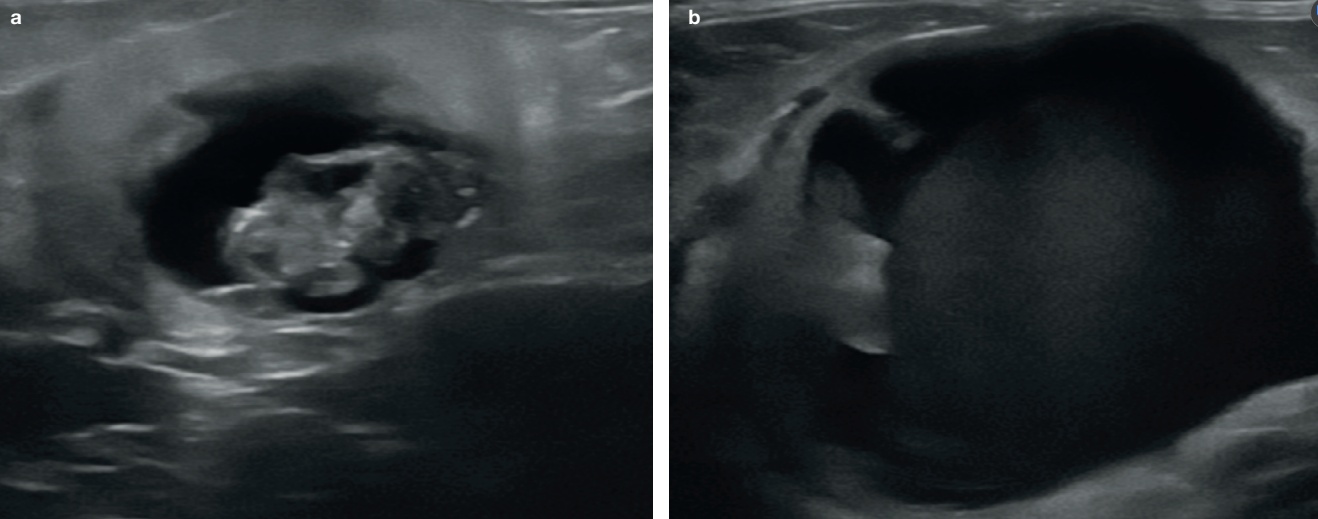

3. 방광의 스캔

초음파로 방광 크기, 벽의 두께, 장막과 점막의 경계를 잘 관찰할 수 있습니다. 방광은 후복강 내 존재하며 고양이에서 앙와위나 측와위 자세에서 쉽게 영상화됩니다. 다른 장기와 같이 2개의 직각 방향으로 스캔(시상면, 등쪽면 혹은 가로면)하며, 스캔 시 소변이 적절히 있어야 점막과 벽의 두께를 측정할 수 있습니다(그림 6).

방광의 벽은 4개의 층인, 점막층(저에코), 저막하층(고에코), 근육층(저에코)와 장막층(고에코)으로 구성되어 있습니다.

정상적인 방광의 벽 두께는 팽대되는 정도에 따라서 1.3~1.7 mm로 측정됩니다. 요관이 방광의 삼각부위로 들어가는데 요관의 유두부위가 때로는 벽 등쪽에 작은 모양으로 보입니다(그림7). 그리고 오줌이 이 유두부위를 통해서 방광으로 배출될 때 칼라 도플러로 jet 모양이 보일 수 있습니다(그림 8).